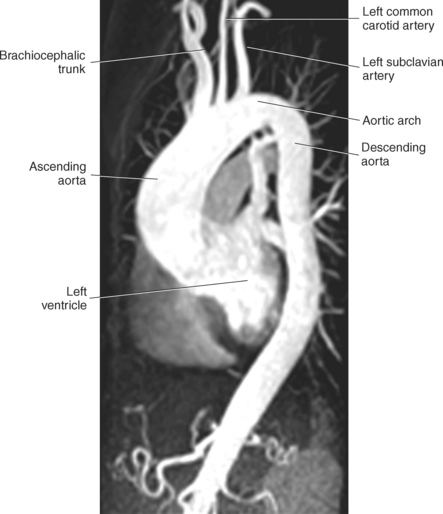

Blood travels to and from the heart through the great vessels, which include the aorta, pulmonary arteries and veins, and superior and inferior venae cavae (Figures 6.54 and 6.55). The aorta is the largest artery of the body and can be divided into the ascending aorta, aortic arch, and descending aorta. The ascending aorta begins at the base of the left ventricle at the level of the sternal angle, then curves superiorly and posteriorly as the aortic arch over the root of the left lung. The top of the aortic arch is approximately at T3 (Figures 6.56 and 6.57). The arch continues as the descending aorta posterior to the left bronchus and pulmonary trunk, on the left side of the vertebral body of T4 (Figures 6.58 and 6.59). The descending aorta passes slightly anterior and to the left of the vertebral column as it descends through the thoracic and abdominal cavities (Figure 6.60). While in the thoracic cavity, the descending aorta is commonly called the thoracic aorta, and while in the abdominal cavity, it is called the abdominal aorta. The pulmonary trunk is the origin of the right and left pulmonary arteries and lies entirely within the pericardial sac. It arises from the right ventricle and ascends in front of the ascending aorta, courses posteriorly and to the left, where it bifurcates at the level of the sternal angle (T4) into the right and left pulmonary arteries (Figures 6.61 through 6.63). The pulmonary trunk is attached to the aortic arch by a fibrous cord called the ligamentum arteriosum, the remnant of an important fetal blood vessel (ductus arteriosus) that links the pulmonary and systemic circuits during fetal development (Figures 6.54 and 6.61). The right pulmonary artery courses laterally, posterior to the ascending aorta and superior vena cava, and anterior to the esophagus and right mainstem bronchus, to the hilum of the right lung. At the root of the right lung, the right pulmonary artery divides into two branches, with the lower branch supplying the middle and inferior lobes and the upper branch supplying the superior lobe (Figures 6.61 through 6.64). The left pulmonary artery, shorter and smaller than the right, is also the most superior of the pulmonary vessels. It travels horizontally, arching over the left mainstem bronchus, and enters the hilum of the left lung just superior to the left mainstem bronchus (Figures 6.61 through 6.64). Within the lungs, each pulmonary artery descends posterolateral to the main bronchus and divides into lobar and segmental arteries, continuing to branch out and to follow along with the smallest divisions of the bronchial tree (Figures 6.61 and 6.64). Located inferior to the pulmonary arteries are the four pulmonary veins, two each (superior and inferior) extending from each lung to enter the left atrium (Figures 6.54, 6.55, 6.61, and 6.64 through 6.68). They commence in a capillary network along the walls of the alveoli, where they are continuous with the capillaries of the pulmonary arteries. The venous capillaries merge to form small vessels that unite successively to eventually form a single trunk for each lobe: three for the right and two for the left lung. Frequently the trunk from the middle lobe of the right lung unites with the trunk from the upper lobe, forming just two trunks on the right side prior to entering the left atrium. The right superior pulmonary vein collects blood from the upper lobe segments of the right lung and passes anterior and inferior to the right pulmonary artery, behind the superior vena cava. The right inferior pulmonary vein receives blood from the right lower lobes of the lung and crosses behind the right atrium to the left atrium (Figures 6.61 and 6.69 through 6.71). The left superior pulmonary vein receives blood from the left upper lobe of the left lung and courses anterior and inferior to the left main bronchus as it enters the left atrium. The left inferior pulmonary vein drains the inferior lobe of the left lung and passes toward the left atrium anterior to the bronchi (Figures 6.61 and 6.72 through 6.74). The pulmonary veins course more horizontally than the pulmonary arteries and are ultimately oriented toward the left atrium. At the root of the lungs, the pulmonary veins are anterior to the pulmonary arteries, which are anterior to the bronchus. While within the lungs, the branches of the pulmonary arteries are anterior to the bronchi, which are anterior to the pulmonary veins. The superior and inferior venae cavae are the largest veins of the body. The superior vena cava is formed by the junction of the brachiocephalic veins, posterior to the right first costal cartilage, and carries blood from the thorax, upper limbs, head, and neck (Figure 6.24). As it travels inferiorly, it is located posterior and lateral to the ascending aorta before entering the upper portion of the right atrium (Figures 6.54 through 6.59). The inferior vena cava is formed by the junction of the common iliac veins in the pelvis and ascends the abdomen to the right of the abdominal aorta and anterior to the vertebral column. It passes through the caval hiatus of the diaphragm and almost immediately enters the inferior portion of the right atrium (Figures 6.75 and 6.76).

The three main branches of the aortic arch are the brachiocephalic trunk, left common carotid artery, and left subclavian artery (Figure 6.84). The brachiocephalic (innominate) trunk is the first major vessel and the largest branch arising from the aortic arch. It ascends obliquely to the upper border of the right sternoclavicular joint, where it divides into the right common carotid and right subclavian arteries (Figures 6.85 and 6.86). The right common carotid artery ascends the neck lateral to the trachea to the level of C4, where it divides into the right external and internal carotid arteries. The right subclavian artery curves posterior to the clavicle into the axillary region, where it becomes the right axillary artery. The left common carotid artery is the second vessel to branch from the aortic arch. It arises just behind the left sternoclavicular joint and ascends into the neck along the left side of the trachea to the level of C4, where it bifurcates into the left external and internal carotid arteries. The left subclavian artery arises from the aortic arch posterior to the left common carotid artery and arches laterally toward the axilla in a manner similar to that of the right subclavian artery, where it continues as the left axillary artery (Figures 6.85 through 6.88). The right and left internal thoracic arteries arise from the respective subclavian artery at the base of the neck. They run deep to the ribs, just lateral to the sternum, to supply blood to the anterior portion of the thorax (Figure 6.89). The common carotid arteries supply blood to the head and neck, whereas the subclavian arteries supply blood to the upper extremities.